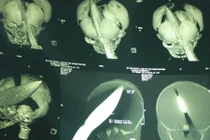

| Công an đọc lệnh bắt nghi can Nguyễn Thị Vân vụ bé trai bị đâm xuyên đầu. |